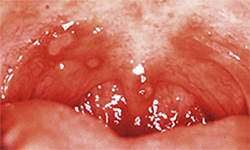

コプリック斑

- [好発部位]

- 頬粘膜にみられる。

- [症状]

- はじめの2〜3日はかぜと同じ症状で、3〜4日で口の中の頬にコプリック斑(白 い斑点)が出現する。これが出れば「はしか」の診断となる。5〜7日で最盛期となり、体や手足、顔に発疹が広がり高熱や強い咳が出る。発疹出現から4〜5日(発病後8〜10日)で解熱し始める。

- [治療]

- 基本的には解熱剤等の対症療法が中心となる。